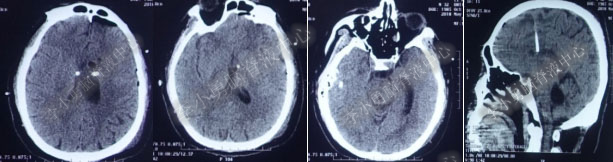

2016年5月9日因“间断性眩晕半月,恶心呕吐一周”以“梗阻性”脑积水,第1次住入北京某企业三级医院神经外科内镜组。2016年5月10日(入院后第2天)行头部MRI(图-1)检查示脑室系统扩张。

图-1:2016年5月10日头部MR

术后7天(2016年5月18日),症状有所缓解,复查头部MRI(图-2)幕上脑室较术前缩小,但是“四脑室仍扩张”,医生认为 “正常”于术后8天(2016年5月19日)出院。

图-2:2016年5月18日头部MRI